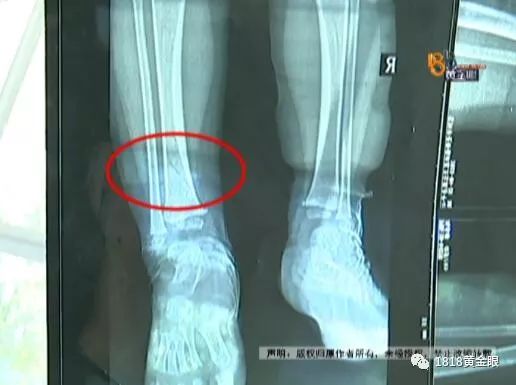

陈女士拿出第二家医院的CT片,孩子左脚靠近脚踝处的胫骨有一处裂缝,这跟第一次在富阳骨伤医院的检查结果完全不同。